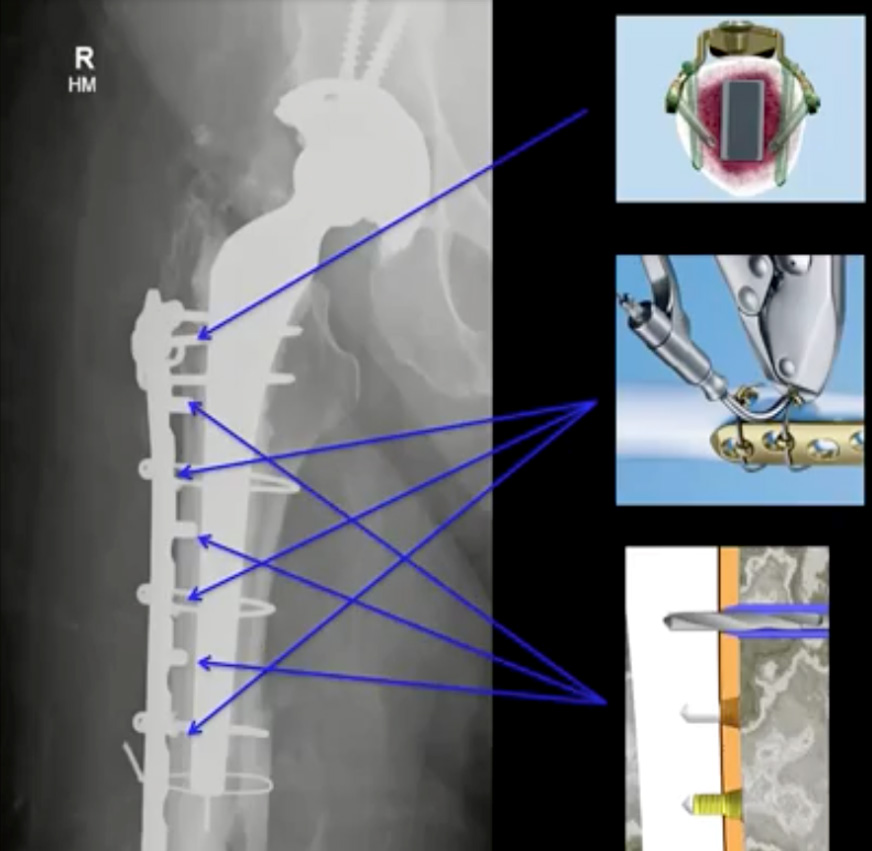

After the plate is fitted to the contours of the femur and roughly in place, cerclage wires can be inserted around the femur. This requires using curved trocars to encircle the femur then feeding cerclage wire through. Minimally invasive techniques such as this shorten operative time, reduce bleeding and minimize fracture exposure. In the diagram above, the upper-right illustration shows how variable-angle screws can be oriented both to maximize the implant’s stability and to screw beside the implant stem.